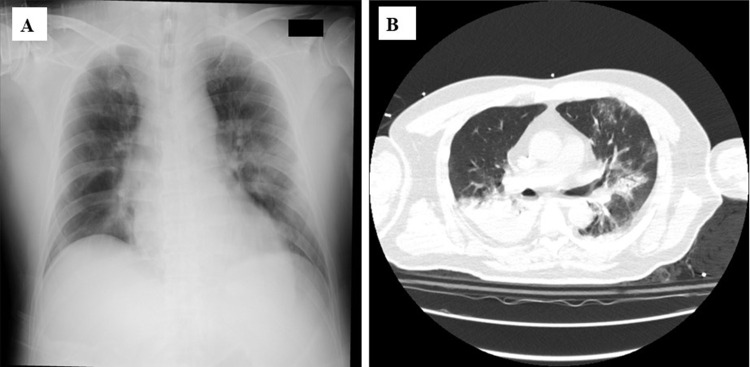

Three cases of severe influenza that required ventilator management in the 2024-2025 season, which was a major influenza season in Japan, are presented. Case 1: A 54-year-old man with obesity developed lobar pneumonia as a result of severe community-acquired pneumonia (CAP) secondary to methicillin-susceptible Staphylococcus aureus (MSSA), as confirmed on sputum culture. The nasal swab was positive for influenza A antigen. Intravenous peramivir and piperacillin/tazobactam were administered for 2 days followed by lascufloxacin and linezolid for 2 weeks. Veno-venous extracorporeal membrane oxygenation (VV-ECMO) was also performed. Case 2: A 63-year-old man with multiple myeloma and chronic kidney disease developed severe pneumonia as a result of CAP. Although influenza A antigen was detected, no bacteria were isolated from his specimens. He showed severe hypoxia and massive ground-glass opacities (GGOs) in both lung fields, but he recovered after administration of peramivir and levofloxacin with prednisolone for 2 days and 2 weeks, respectively, with non-invasive positive pressure support. Case 3: A 43-year-old man without any related medical history developed severe heart failure with mild bronchopneumonia and was admitted to our hospital. Acute heart failure caused by myocarditis and CAP due to influenza A were suspected and treated effectively with peramivir and a percutaneous ventricular assist device (IMPELLA), which involved an auxiliary circulating pump with veno-arterial ECMO (VA-ECMO) for 1 day and 2 weeks, respectively. In three middle-aged patients, influenza virus may have accelerated pneumonia/heart failure. All three patients had not received influenza vaccines and were not elderly. Although the emphasis on most vaccines has decreased after the COVID-19 pandemic appears to have subsided, we should stress the importance of influenza vaccines and improvement of critical care protocols, because severe influenza can be a concern for young and middle-aged adults during the influenza season after the post COVID-19 pandemic period.